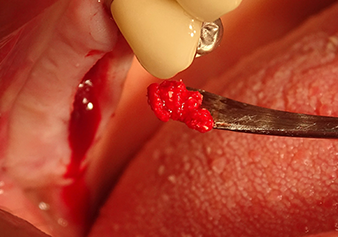

Затем, с помощью инструмента I2A (диаметр 2,0 мм), дно пазухи перфорировалось периодически и в минимально возможном диапазоне. Этот специфический пьезохирургический метод гарантирует, что мембрана Шнейдера не будет повреждена. При использовании Z25P, мембрана уже была слегка приподнята охлаждающей жидкостью, подаваемой через наконечник инструмента (рис. 3). Во избежание высокого давления в ложе имплантата, количество охлаждающей жидкости составляло не более 50%.

Подготовка ложа имплантата и наращивание

После промежуточного контроля (рис. 4) был проведен еще один этап подготовки (рис. 5). За тем, с помощью гидравлического инструмента Z35P мембрана была поднята в нужное положение (рис. 6 и 7). Далее, следовала дальнейшая пьезохирургическая подготовка ложа для имплантата, завершенная с помощью ротационного бора и лопаточной фрезы до диаметра имплантата 4,8 мм. Перед установкой имплантата под мембрану Шнейдера был введен аугментационный материал (размер частиц около 0,8-1,6 мм) (рис. 8).